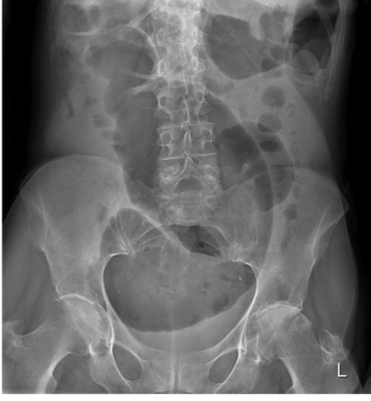

Patient with severe abdominal pain. What is the cause of pain demonstrated on this abdominal X-ray?

Caecal volvulus

Normal appearances

Pneumoperitoneum

Small bowel obstruction

Toxic megacolon